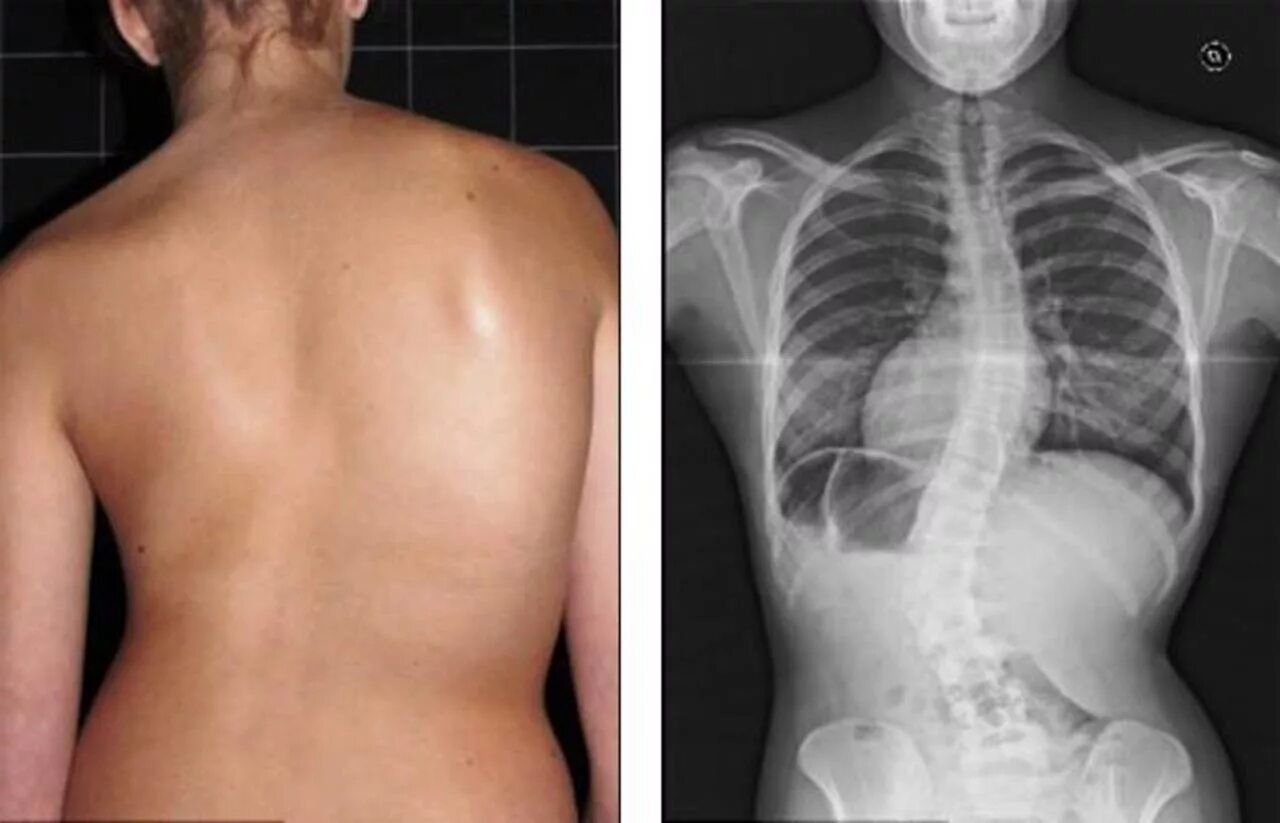

Сколиоз 2ст